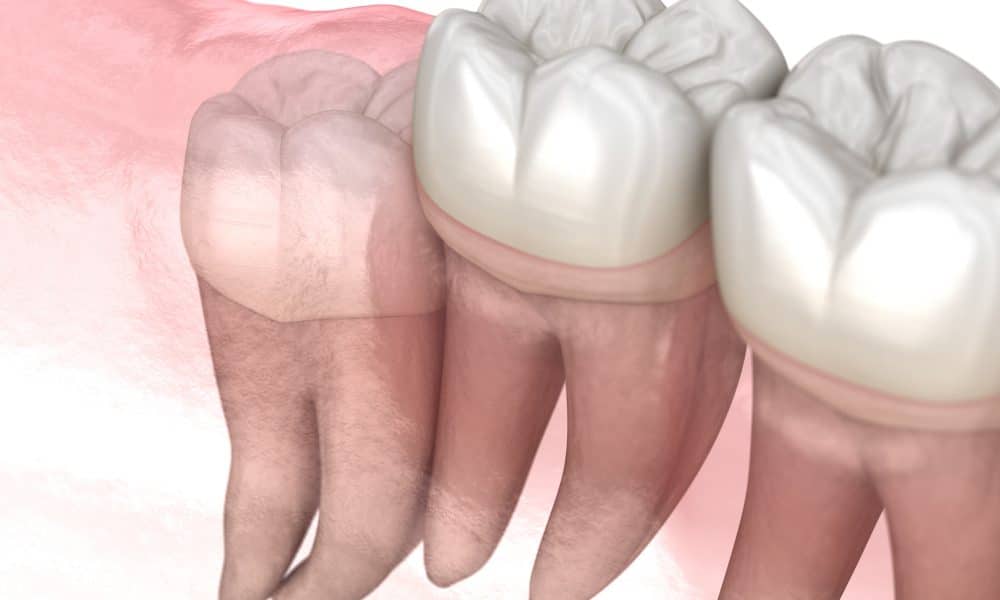

An impacted tooth is a tooth that is stuck and cannot erupt into the correct position. Impacted wisdom teeth are among the most commonly impacted teeth because the jaw often does not have enough room in the back of your mouth to fit the third molars.

When a wisdom tooth is impacted, it may be trapped under gum tissue, embedded in surrounding bone, or positioned against nearby teeth. These situations can increase the risk of dental complications and may require oral surgery for safe removal.

Common Types of Impaction

During your evaluation, we look closely at the position of your wisdom teeth and how much of the tooth is covered by gum tissue or bone.

The tooth is covered by gum tissue and there is not enough room for the gums to retract. This can create cleaning challenges and irritation in the back of the mouth.

The tooth partially erupts but does not reach a functional chewing position. It often traps food and bacteria, raising the risk of gum disease, bad breath, and tooth decay.

There is no space for eruption and the tooth remains embedded in the jawbone. This often requires a more involved surgical procedure due to the tooth’s position and surrounding hard tissue.